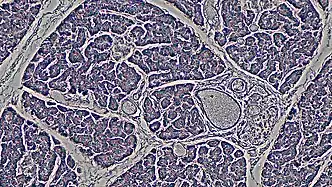

The ductal pancreas network originates from the central pancreatic duct—this main duct with the bile duct opens into the duodenum. The ductal cells of the main pancreatic duct are bound by connective tissue and produce a columnar epithelium.[3] Interlobular ducts originate from the main pancreatic duct and connect the various pancreatic lobes. In these lobes, the intercalated ducts expel acini. Meanwhile, the ductal cells of these intercalated ducts create a simple squamous epithelium that rapidly converts into simple cuboidal, and connective tissue also surrounds them.[3] As the ducts grow larger, the epithelium becomes cuboidal or columnar (when large in diameter, the ducts become stratified cuboidal), and connective tissue surrounds them. Pancreatic ductal cells are very similar to ductal cells of other exocrine glands (liver, bile duct, salivary glands).[3] Because of this, a common diagnosis affects these cells: cystic fibrosis.

The largest network branches in this system contain goblet cells that interact with ductal cells, making up about 2% of this structure—these cells aid mucin assembly. Furthermore, unlike other exocrine glands, the pancreas does not have myoepithelial cells around the ducts.[3] Ductal cells have a single cilium that is made up of nine peripheral doublets but does not have a central microtubule. This cilium is considered vital for perceiving flow in ducts.[3]

Morphology is what identifies ductal cells. However, there is barely anything to differentiate pancreatic ductal cells from other bodily ductal cells.[6] There is still a lot unknown about these ductal cells. Their molecular identity still needs to be improved; more knowledge is necessary regarding stage-specific markers and the regulators of ductal cell development. It recently was discovered that the ducts start as separate microlumens in a stratified epithelium that expand, attach, and resolve to form the pancreatic ducts. These cells work with intercalating ducts that link to distinct acini and are within the larger ducts in the two core pancreatic ducts (dorsal and ventral duct) that drain into the intestine.[6]